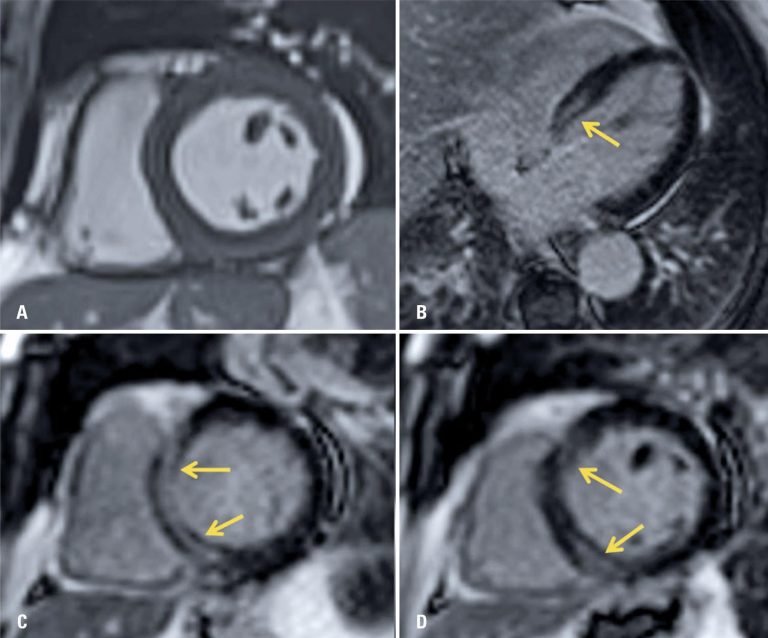

Figura 3

Imagens de ressonância magnética cardíaca na cinerressonância magnética no eixo curto. (A) e sequências de realce miocárdico tardio no eixo longo quatro câmaras; (B) e eixo curto; (C e D) mostrando áreas de realce tardio de padrão não isquêmico na parede septal basal do ventrículo esquerdo (setas), achados que, no contexto clínico, sugerem processo inflamatório/infeccioso (miocardite)